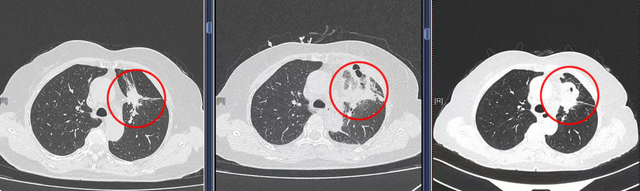

手术当天,在CT实时引导下,穿刺针顺利进入肿瘤核心区域。随着微波能量释放,局部迅速形成高温场,短短数分钟便覆盖了整个病灶。沈女士全程清醒,仅接受局部麻醉,呼吸平稳,术中配合良好。术后恢复顺利,第四天即可出院。随访影像显示,消融区肿瘤完全坏死,这一结果让她和家人如释重负。

▲胸外科赵建华医师为患者行CT引导下肺微波消融术